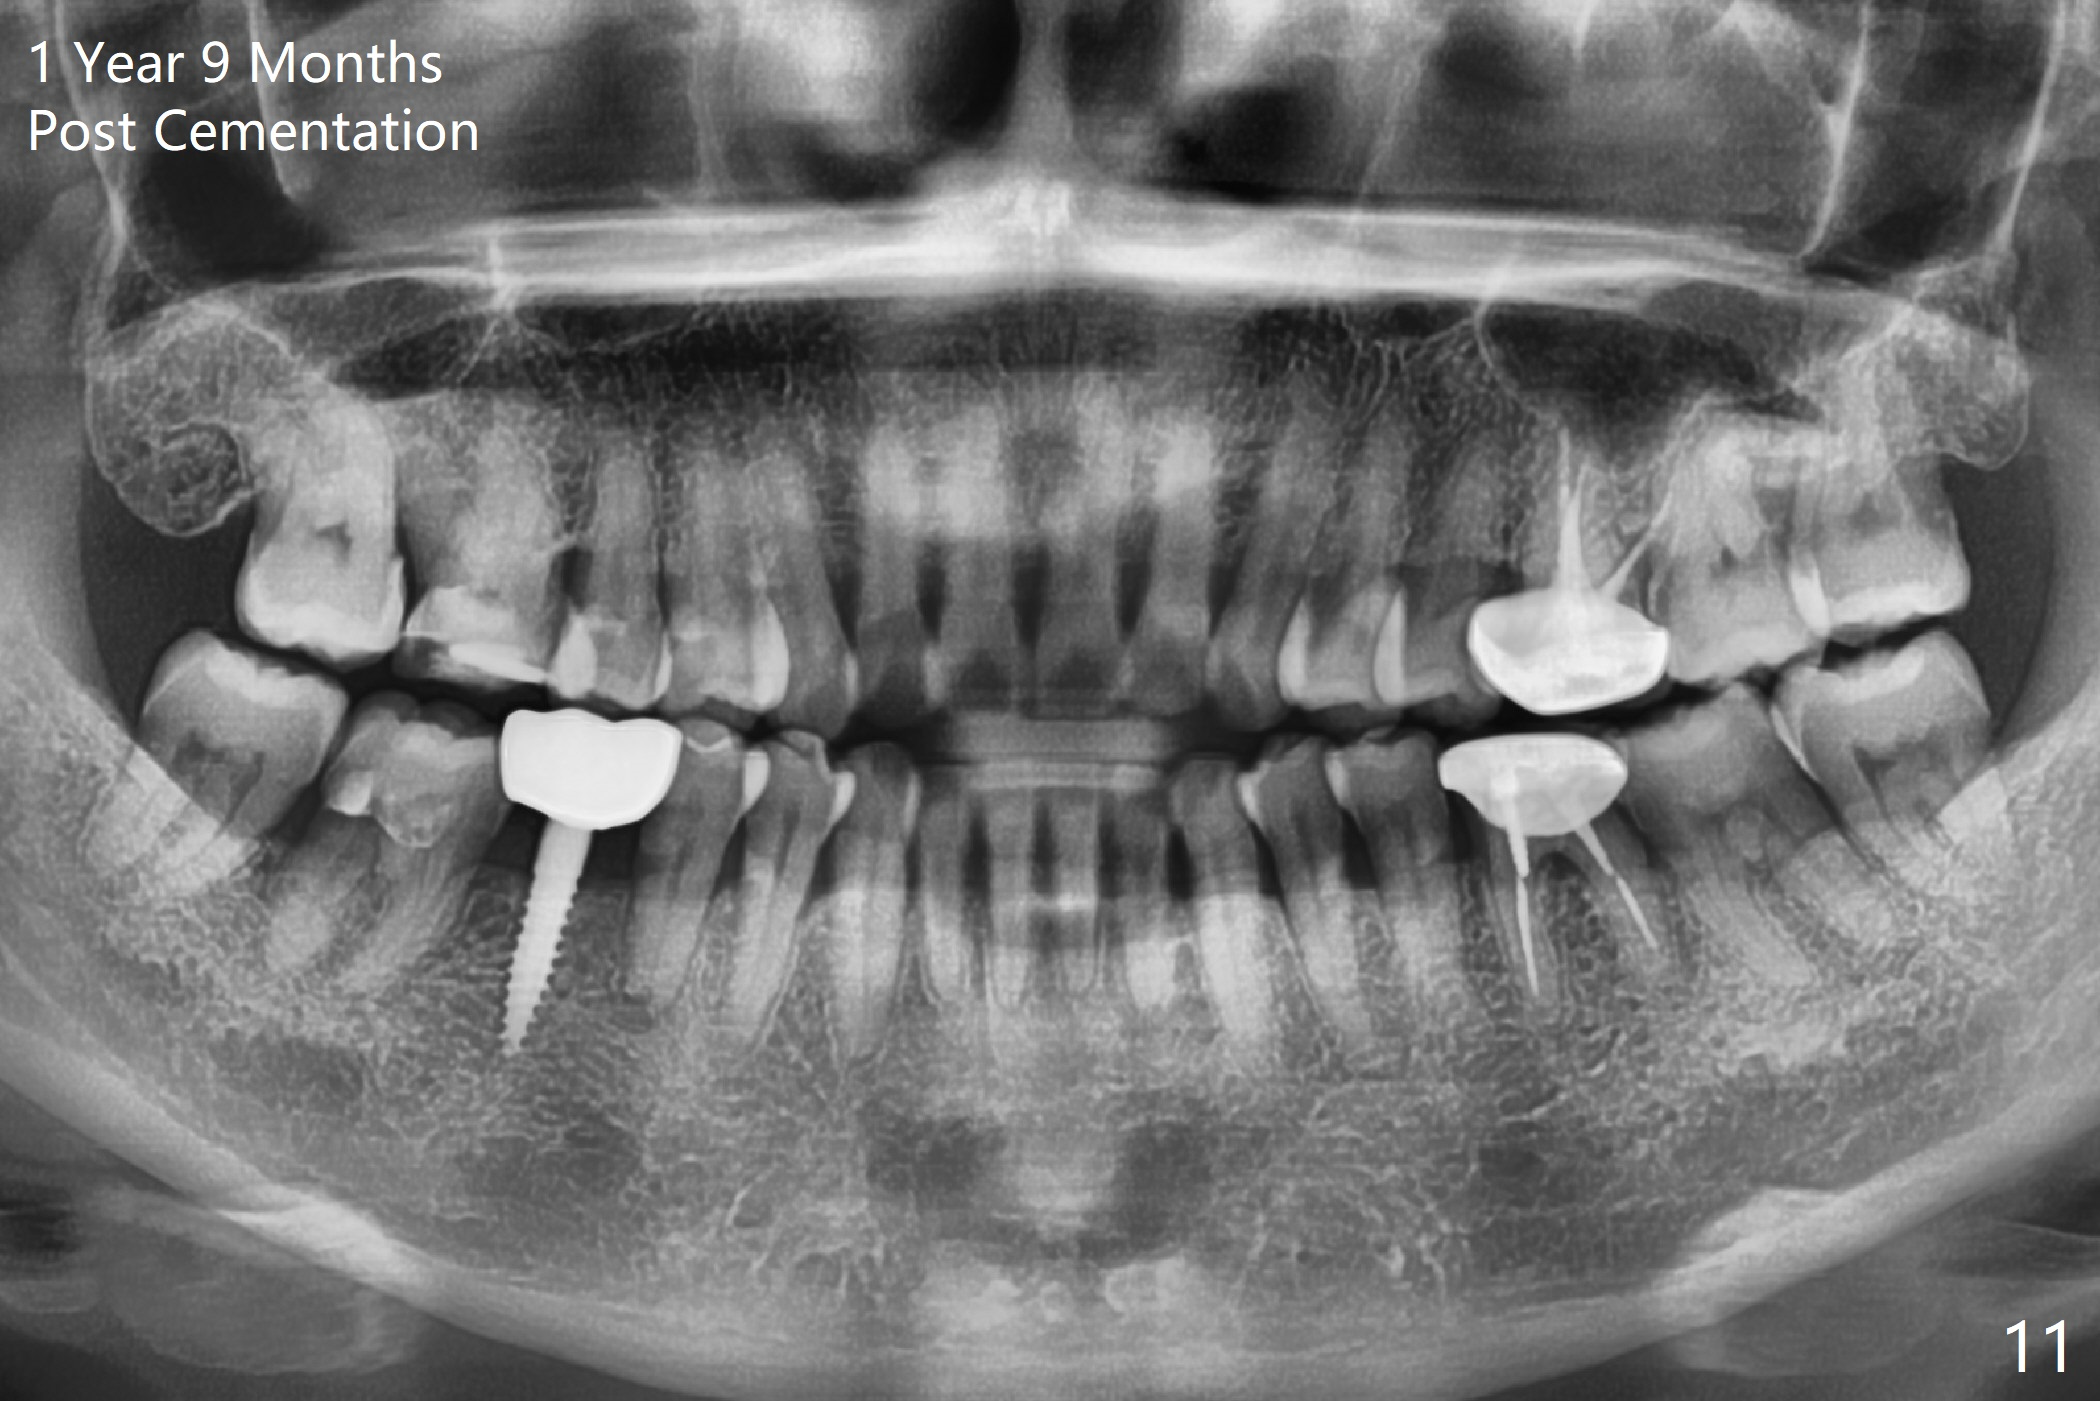

Before crown cementation, the ridge looks wider (Fig.7 *) than preop. There is no diastema between #31 and 32 (Fig.8, 17 days post cementation). The patient is pleased with less food impaction. The total treatment (including ortho) is 16 months. It appears that distalization of #29 is not effective to gain the bone width. In fact simultaneous GBR with implant placement is much more efficient. There is no bone loss 3 months post cementation (Fig.9). The gingiva looks healthy 10 months post cementation (Fig.10). The implant crown is functioning 1 year 9 months post cementation (Fig.11) and 3 years 7 months post cementation (Fig.12).